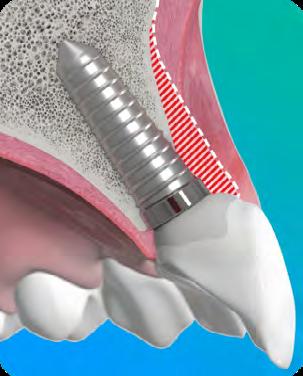

Buccal gap bone grafting (with low substitution material)

While implant positioning is critical, it does not prevent post-extraction remodeling. Biomaterials play a key role in managing the peri-implant gap and maintaining long-term hard- and soft-tissue stability.

“Placing an implant does not stop facial bone remodeling. The implant is a passive occupant — reconstruction with biomaterials is required to maintain volume and long-term hard- and soft-tissue stability.”

Fill the Gap: stabilize the clot and support ridge contour stability.

Fill + Protect: stabilize the clot and limit soft-tissue ingrowth to support esthetics.